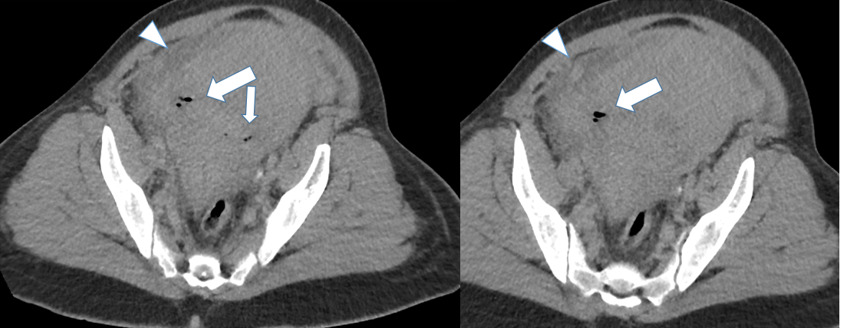

The initial impressions of the axial and coronal CT images revealed dilation of the right ovarian vein in addition to intraperitoneal fluid accumulation on the right side (Fig. 1-2). Portovenous and delayed phase images did not demonstrate contrast pooling or persistent hyperattenuation to suggest hyperacute hemorrhage (Fig. 3-4). Additionally, there was evidence of peritoneal air present between the uterine myometrium and ovarian vasculature most notable along the right aspect of the anterior inferior uterus. A contour abnormality along the right parasagittal lower uterine segment was also noted and interpreted as a uterine defect without signs of free intraperitoneal hemorrhage. In conjunction with her clinical picture, these radiologic findings raised our suspicion for a contained uterine rupture although there were no pathognomonic imaging findings to confirm an associated retroperitoneal hematoma. The patient was urgently taken to the operating room for an exploratory laparotomy to confirm the diagnosis and to manage surgically if indicated.

Uterine rupture was highly suspected even prior to the exploratory laparotomy due to the presence of air between the uterine myometrium and the ovarian vessels. Figures 1-4 describe CT findings consistent with uterine rupture. This is the first case report of a uterine rupture being managed conservatively similarly to previously described management options for contained uterine hematomas.